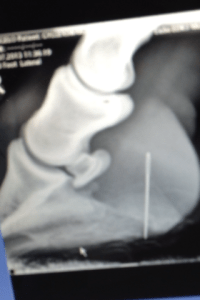

Looking forward to competing Donald on the second day added to the huge disappointment when they found Donald in the stable with a swollen hind leg and bearly being able to put any weight on it. They immediately got the Hartpury vet on site to have a look and see if he could find out what could be wrong. It eventually came about that he could see a tiny plaiting needle head stuck in Donald’s frog which must have been dropped in the bed by a previous competitor. In order not to cause any possible further damage it was decided to xray the foot and see where exactly the needle had buried itself. Luckily (if you look at it that way!) the needle had gone straight up and slightly back missing any vital tendons, ligaments and burseries. The vet was able to pull the needle straight out and treat the foot very carefully not allowing any bacteria to get into the frog as this could be fatal.